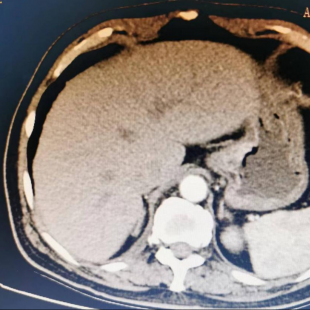

临床资料:患者男性,76岁,主诉:“呕血6天,确诊胃癌2天。”患者于6天前无明显诱因出现呕血,量约20ml,伴乏力,无腹痛、腹胀,无发热。患者于当地医院行胃镜+病理检查示:胃腺癌。遂来我院进一步治疗,腹部CT示:贲门胃小弯侧胃壁增厚,局部较明显欠均匀强化,考虑Ca(图a)。入院完善相关检查予手术治疗。

图a 腹部CT示胃小弯侧胃壁增厚